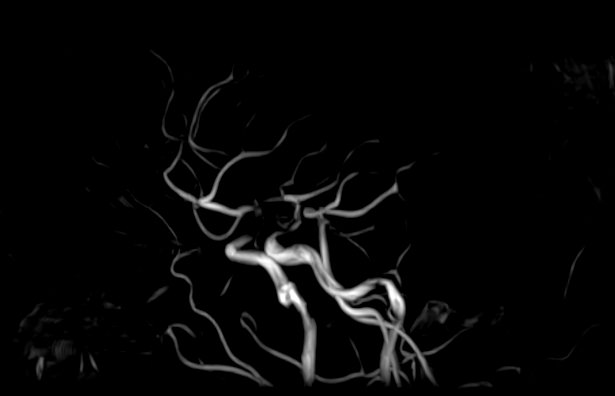

МР-артериография — неинвазивный безопасный метод исследования для диагностики патологии артериальной системы головного мозга. Магнитно-резонансная артериография позволяет получить трехмерное изображение сосудистой системы, кровоснабжающей центральную нервную систему, оценить анатомическое строение артерий головного мозга и функциональные особенности кровотока.

С помощью электромагнитных волн томограф послойно сканирует структуры исследуемого органа, затем посредством компьютерных программ преобразует полученные данные в трехмерное изображение. При этом на снимке видна только сосудистая система без окружающих тканей. Таким образом, сканирование в режиме ангиографии позволяет визуализировать артерии и вены головного мозга без контрастирования.